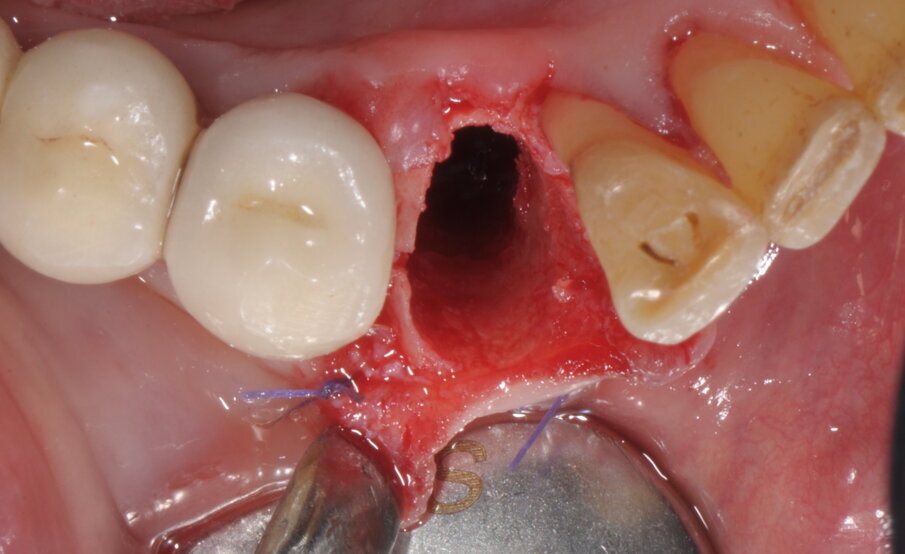

Il caso clinico che andremo a descrivere vede interessata una paziente di anni 69, di sesso femminile, in buona salute, non fumatrice, con frattura del 4.3 ricostruito in precedenza con una ricostruzione diretta in resina composita dopo trattamento endodontico. In accordo con la paziente abbiamo elaborato un piano di trattamento che prevedeva l’estrazione della porzione radicolare residua del canino inferiore di destra, l’inserimento simultaneo di un impianto osteointegrato e un carico protesico immediato. In anestesia locale è stata praticata un’incisione intrasulculare, con minimo scollamento dei tessuti molli, per accedere alla superficie di frattura (Fig. 1). La procedura chirurgica, valutato lo spessore ridotto della corticale vestibolare in accordo con i protocolli PIEZOSURGERY applicati alle estrazioni, ha previsto la regolarizzazione della linea di frattura apicalmente alla giunzione amelo-cementizia, mediante un inserto OT7 e, successivamente, un frazionamento radicolare in direzione mesio-distale con inserto OT7S-3 (Figg. 2, 3).

Fig. 2

Fig. 3